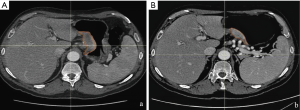

In our experience, delta radiomics, defined as the calculation of the modification of texture parameters before and after NAC, has shown the potentiality to predict histopathological response and patient outcome, overcoming the limit of a model based only on pre or post-treatment radiomic features (9). We have preliminary analyzed a homogeneous cohort of 23 patients with biopsy proven resectable AGC (≥ T3 or N+), treated with NAC and radical surgery. Gastric lesion, defined as gross tumour volume (GTV) was contoured on every slice of pre and post NAC contrast enhanced CT scan, obtaining a 3D region of interest (3D-ROI) with the contouring software RayStation, using a method already validated in different settings (10). Finally, a correlation between the texture parameters [histogram, shape and grey-level co-occurrence matrix (GLCM)] extracted from the 3D-ROI and the complete pathological response (ypCR: tumour regression grade 1 according to Becker et al.) was searched. In our preliminary case population only three patients showed a ypCR, and only delta parameters entropy (P=0.003), GLCM-contrast (P<0.001), GLCM-entropy (P=0.004), GLCM-dissimilarity (P=0.001) were correlated with this outcome at univariate analysis whereas at multivariate analysis, the only parameter that showed a significant correlation was the delta GLCM-contrast (R2: 0.539, sensibility 66%, specificity 100%, AUC 0.733) (Figure 1).